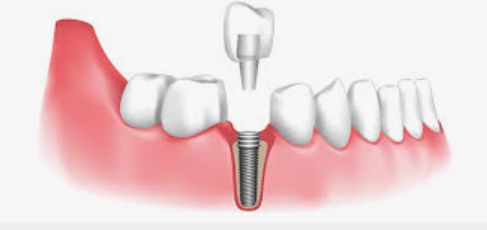

어금니 임플란트 과정

어금니 임플란트의 과정은 여러 단계로 구성되어 있습니다. 어금니 임플란트 가격을 고려한 후, 아래의 단계를 참고하시면 됩니다.

1단계 - 초기 상담: 환자는 치과 의사와 상담을 진행합니다. 의사는 어금니의 상태를 평가하고, X-레이나 CT 스캔을 통해 뼈의 상태를 확인합니다. 이를 토대로 의사는 어금니 임플란트가 적합한 치료 방법인지 판단하며, 필요한 어금니 임플란트 가격을 예상할 수 있습니다.

2단계 - 수술: 치과 의사는 어금니 부위에 조심스럽게 구멍을 내고 임플란트를 삽입합니다. 그 후, 임플란트 주위의 뼈와 임플란트가 안정적으로 결합되도록 치유를 위한 기간을 마련합니다. 이 과정은 일반적으로 수 주에서 몇 개월까지 소요될 수 있습니다.

3단계 - 임시 크라운 부착: 치유 기간 이후, 임플란트와 주변 뼈가 충분히 결합된 것으로 판단되면 임시 크라운을 임플란트에 부착합니다. 이를 통해 환자는 정상적인 식사와 말하기를 할 수 있게 됩니다.

4단계 - 영구 크라운 설치: 뼈와 임플란트가 완전히 결합된 후, 임시 크라운을 제거하고 영구 크라운을 설치합니다. 이 단계에서는 어금니의 자연스러운 외관과 느낌을 제공하여 장기적으로 안정성과 기능성을 보장합니다.